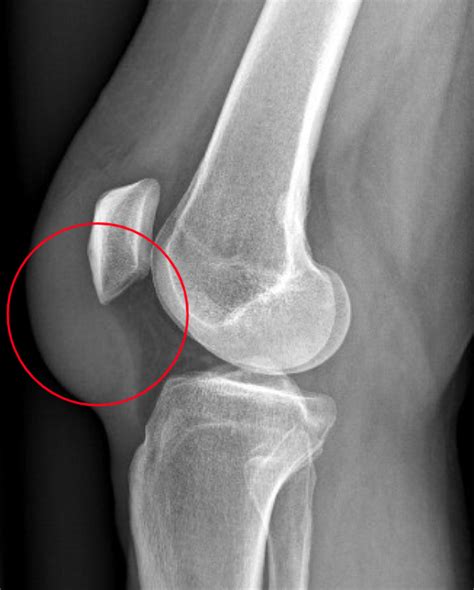

Pre Patellar Bursitis - Patella Conditions - Knee - Conditions

Pre Patellar Bursitis - Patella Conditions - Knee - Conditions ...

Prepatellar Bursitis Treatment | OrthoMA

Prepatellar Bursitis Treatment | OrthoMA